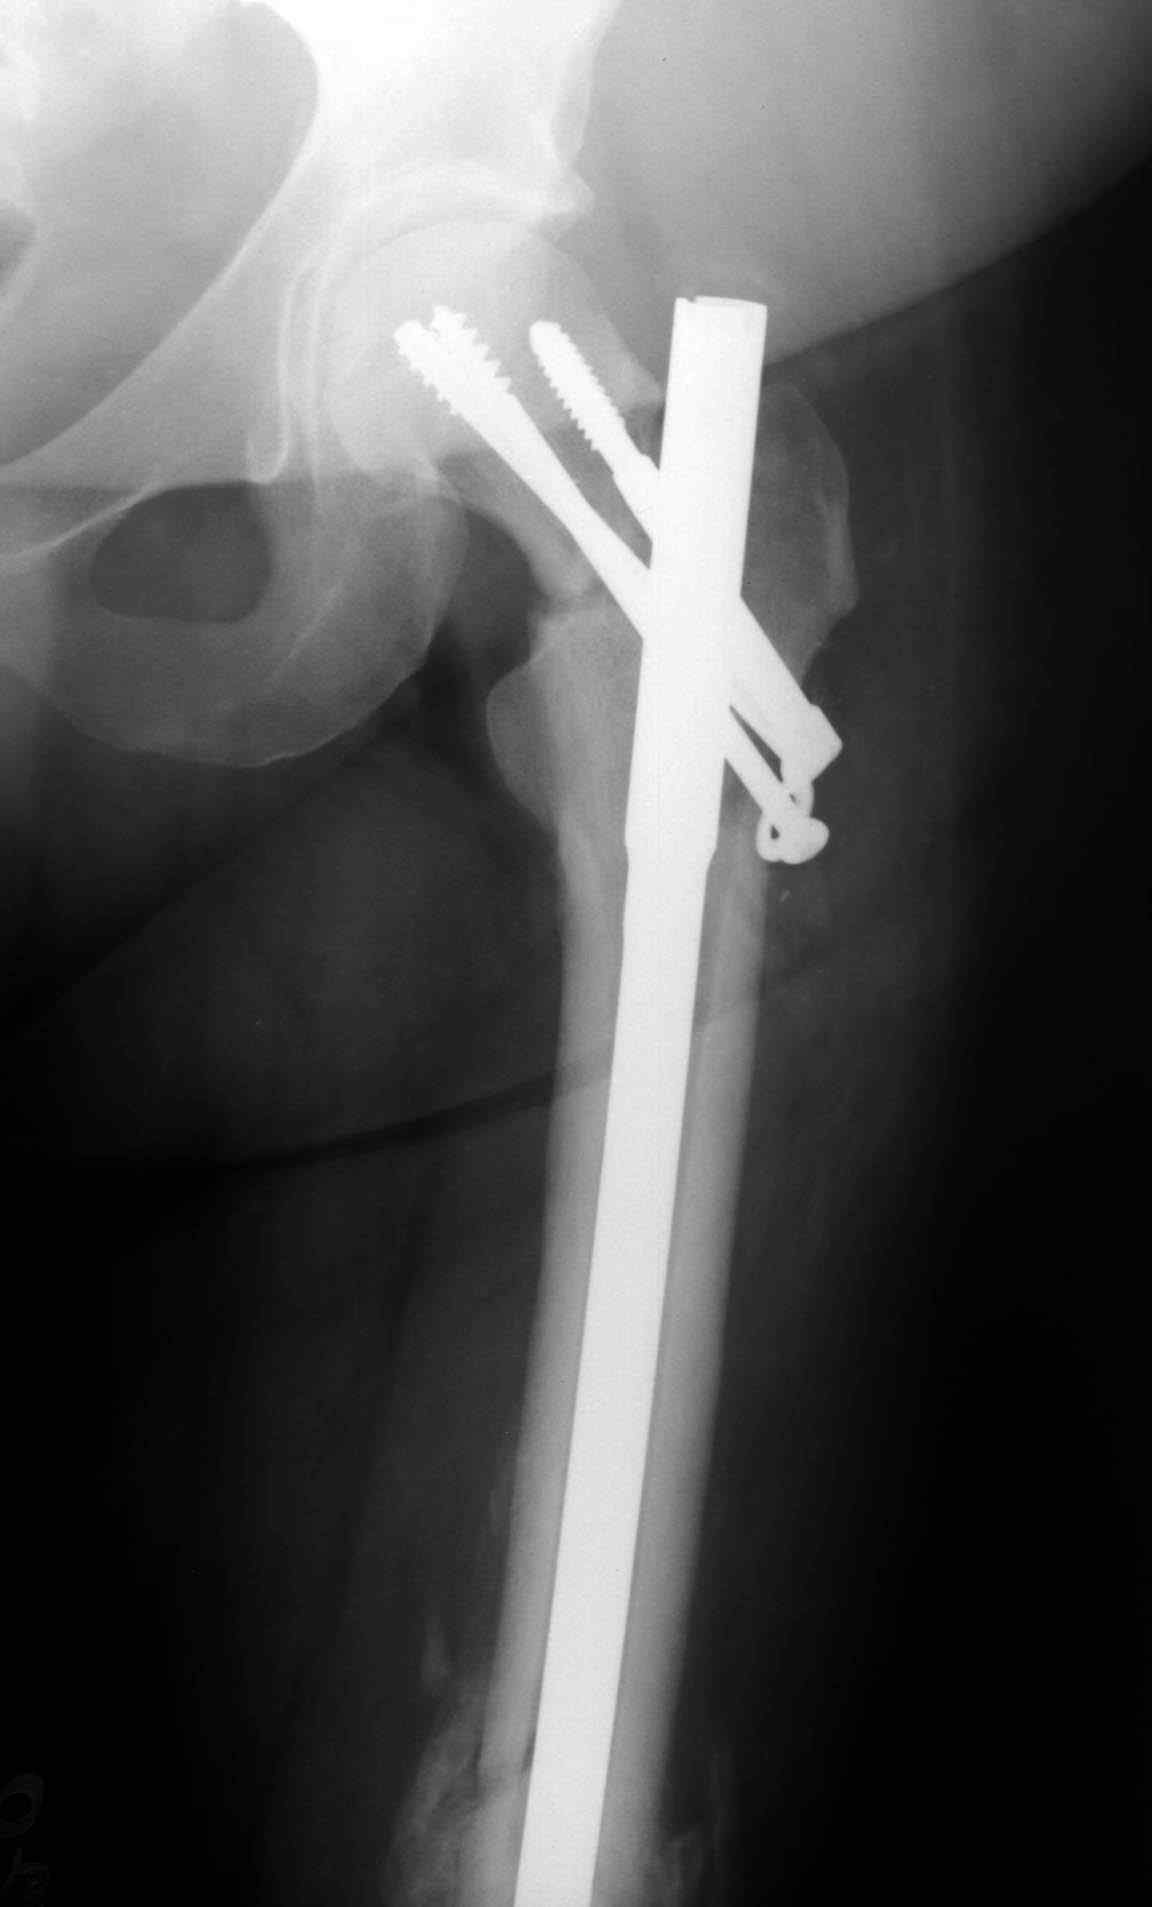

Имя     : missed neck ap.JPG

Тип     : image/jpeg

Размер  : 8243 байтов

Url     : http://weborto.net:8080/pipermail/ortho/attachments/20080114/94c631b9/attachment-0009.jpeg